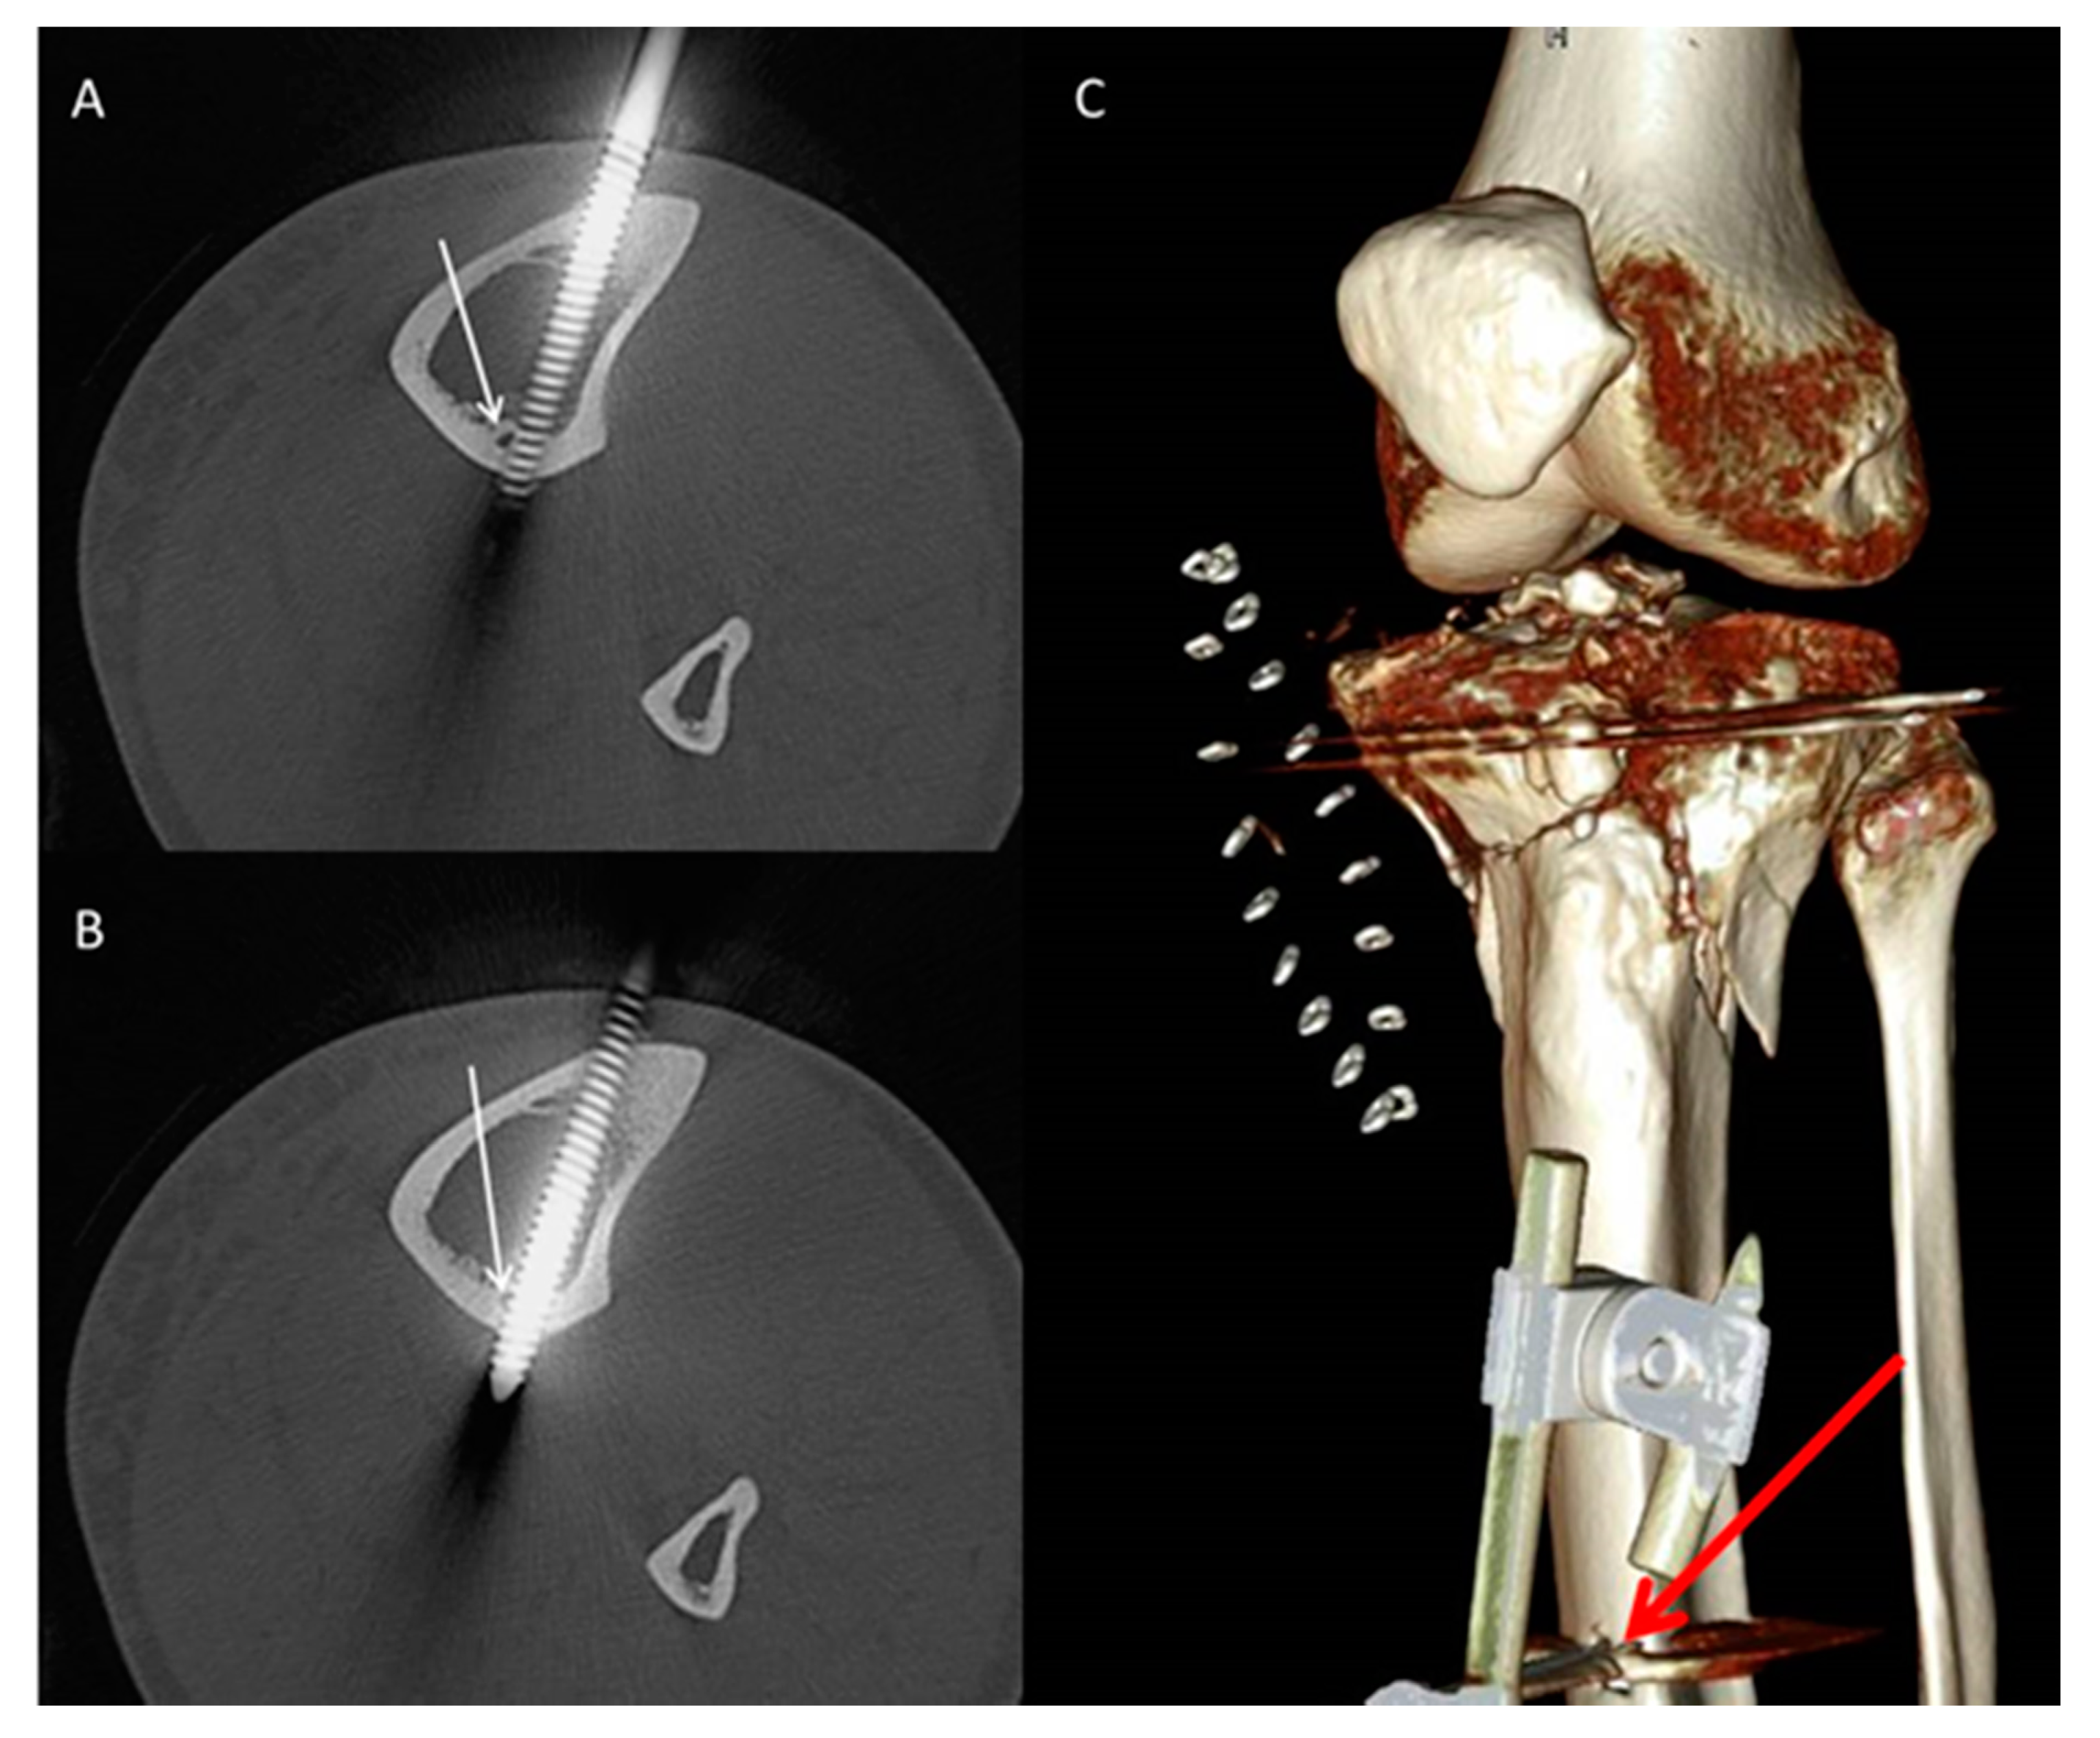

- Pin characteristics (orientation of pin application: anteromedial/tibial crest, anterolateral) and cortical position of the pins (bicortical/monocortical/transcortical) (Figure 2).

- The anatomic relationship between the TNAC and external fixation pin (topography above/below and at the level of the TNA canal, and distance between the pin and medial tibial plateau and/or the medial malleolus) for different fixation and fracture types.